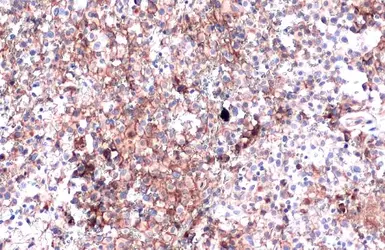

PD-L1 antibody detects PD-L1 protein at cell membrane in human ovarian carcinoma by immunohistochemical analysis.  Antibodies: PD-L1 antibody (GTX104763) diluted at 1:1000, and competitor's antibody diluted at 1:50.

Antigen Retrieval: Citrate buffer, pH 6.0, 15 min